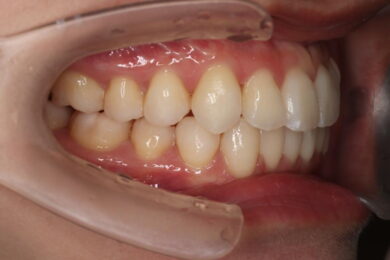

八重歯・叢生 マウスピース矯正(インビザライン)26歳女性 非抜歯

「前歯のガタガタ(叢生)と八重歯を治したい」を主訴に来院された患者様です。上下の歯にIPRを加え、歯列弓の拡大を行い、非抜歯で前歯のガタガタを整えました。顎間ゴムを用い、咬み合わせも改善されています。アライナーの装着時間が長く、チューイをしっかり使用していただけたため、非常に短時間で仕上がりました。

• 治療後